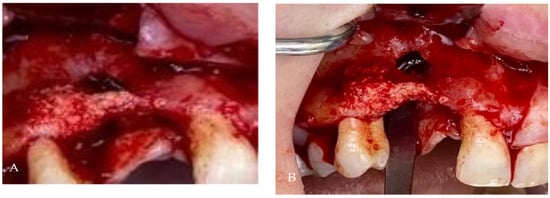

2. Case Presentation